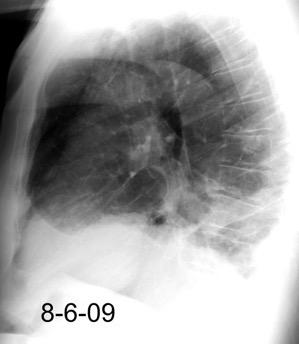

Marzo 2014: Perforación longitudinal distal secundaria a episodio de vómito (síndrome de Boerhaave). Derrame pleural izdo. que evoluciona a empiema.

Wang C-T et al. Tension hydropneumothorax in a Boerhaave syndrome patient: A case report . World J Emerg Med, 2021. Katabathina V et al. Nonvascular, nontraumatic mediastinal emergencies in adults:a comprehensive review of imaging findings. Radiographics. 2011.